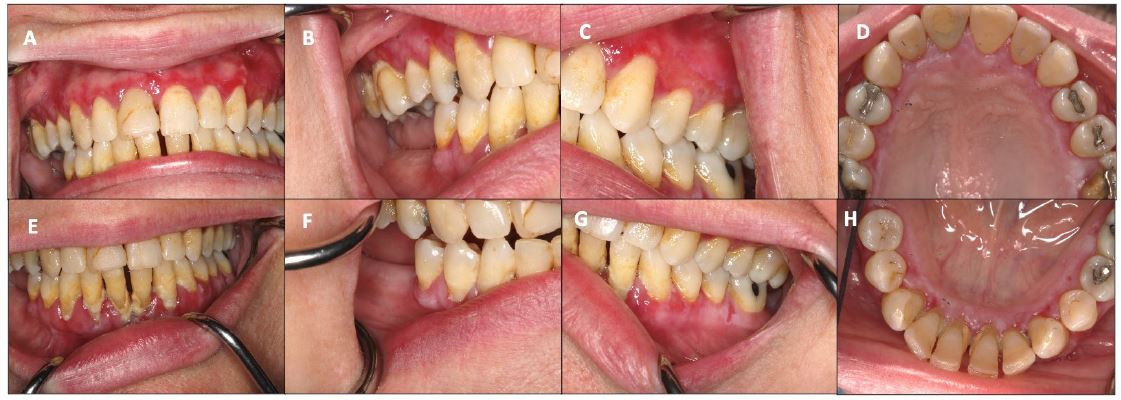

A 58-year-old woman presented to the allergy clinic with an 18-month history of intermittent painful vesicles in her mouth, which she associated with food ingestion. Symptoms started when she took up gardening and began eating more fresh vegetables like tomatoes from her garden. She denied rhinitis, hives, and gastrointestinal symptoms. Medications she was taking included apixaban, atorvastatin, levothyroxine, metoprolol succinate, and trospium. Physical exam showed desquamative gingivitis involving the maxillary and mandibular gingiva (Figure 1). Ocular and skin exams were unremarkable. Diagnostic labs, including complete blood count, ferritin, anti-Ro, anti-La, vitamin B12, and folate were unrevealing. Skin testing to inhalants to evaluate cross-reactivity with oral allergens was uninterpretable due to dermatographism. In vitro respiratory allergy panel showed allergic sensitization to trees, ragweed, and grasses. Patch testing was not performed. Given her presenting symptoms and lack of rhinitis, she was referred to the Oral Medicine clinic. On further questioning, she also reported exacerbation of the rash when consuming cinnamon, cucumbers, almonds, and using mint flavored toothpaste. The differential diagnosis included Oral Lichenoid Contact Reaction (OLCR), Oral Lichenoid Drug Reaction (OLDR), irritant contact dermatitis, and autoimmune blistering disorders such as MMP or Pemphigus Vulgaris (PV). Burning Mouth Syndrome (BMS) was considered, but since BMS presents with normal appearing oral mucosa, it was considered unlikely. Oral Allergy Syndrome (OAS) was also considered, but the patient’s symptoms persisted and did not resolve with avoidance of the suspected foods. The physical exam findings also made this condition unlikely. The final diagnosis of mucous membrane pemphigoid (MMP) was made upon gingival biopsy for routine histopathology and direct immunofluorescence. She was started on clobetasol gel and referred to dermatology and ophthalmology for further management.

Figure 1: Maxillary and mandibular gingiva with erythema and erosions (Figure 1 A-H).